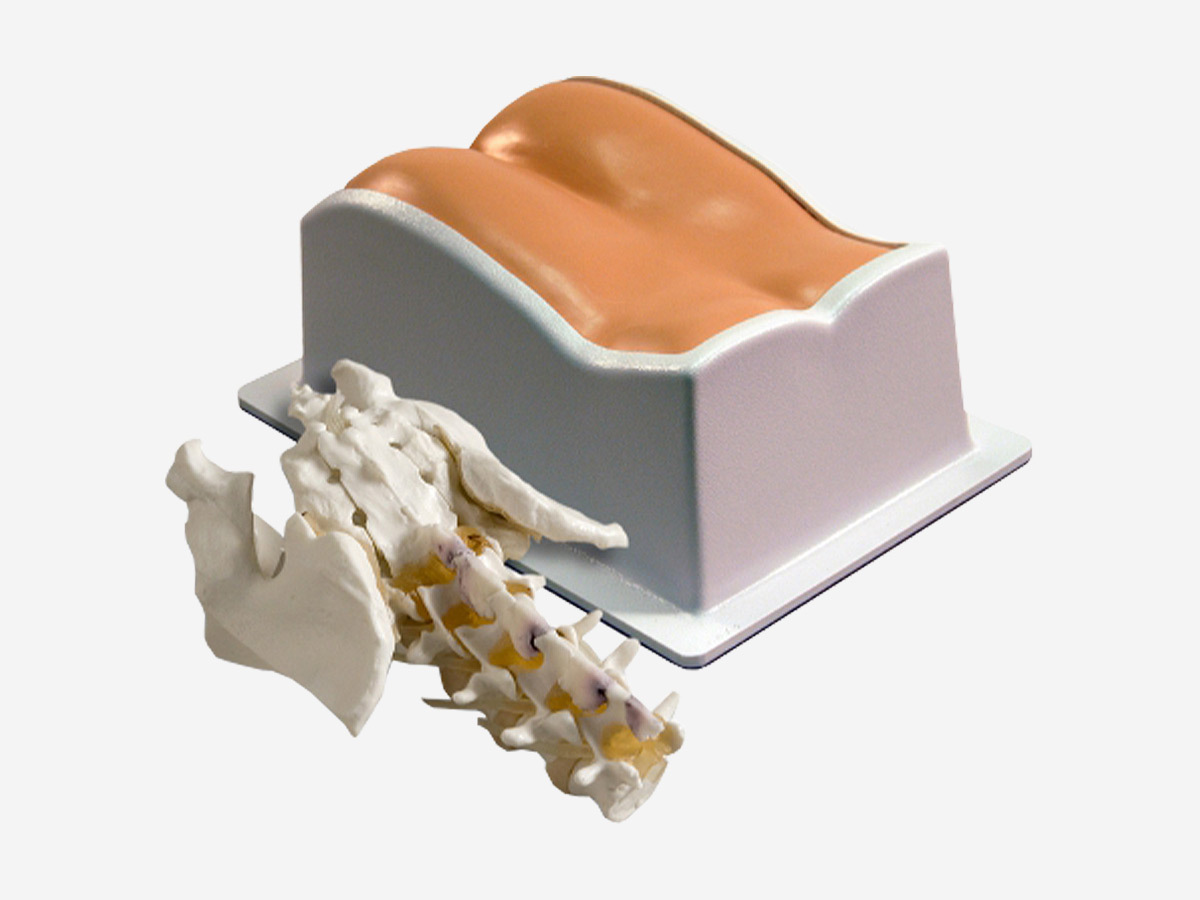

Lumbar Training Phantom

- Realistic needle resistance of each tissue to allow the trainee to “feel” the injection site

- Train many spinal procedures including sacroiliac joint injection, lumbar and caudal epidurals, diskography, block nerves, and facet blocks

- Can be imaged under Fluoroscopy, CT, MR, and ultrasound

Dimensions |

38 cm x 25 cm x 18 cm |

Weight |

19 lbs. (7.1 kg) |

Materials |

Epoxy Resin (bony spinal structures) Urethane (soft spinal structures) Zerdine® (soft tissue) |